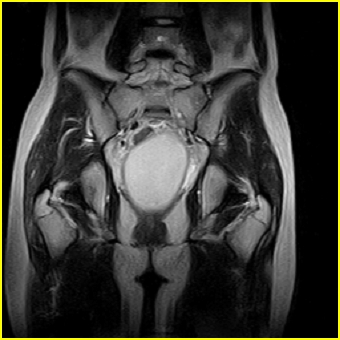

女、15岁、下腹疼痛2天,排尿困难1天。查体:处女膜闭锁,距处女膜约4至5cm处扪及一约5cm直径的圆形包块,张力较高,触痛明显、欠活动。b超提示子宫增大伴宫内增强回声团。

影像意见:子宫直肠陷凹积血。

更正影像意见:阴道积血。

处女膜闭锁,阴道积血

处女膜闭锁,阴道积血,子宫积血.

先天性处女膜闭锁,伴阴道积血,不除外先天性阴道粘液囊肿形成。

阴道积血,子宫积血.

子宫及阴道积血。

处女膜闭锁,伴子宫及阴道积血.